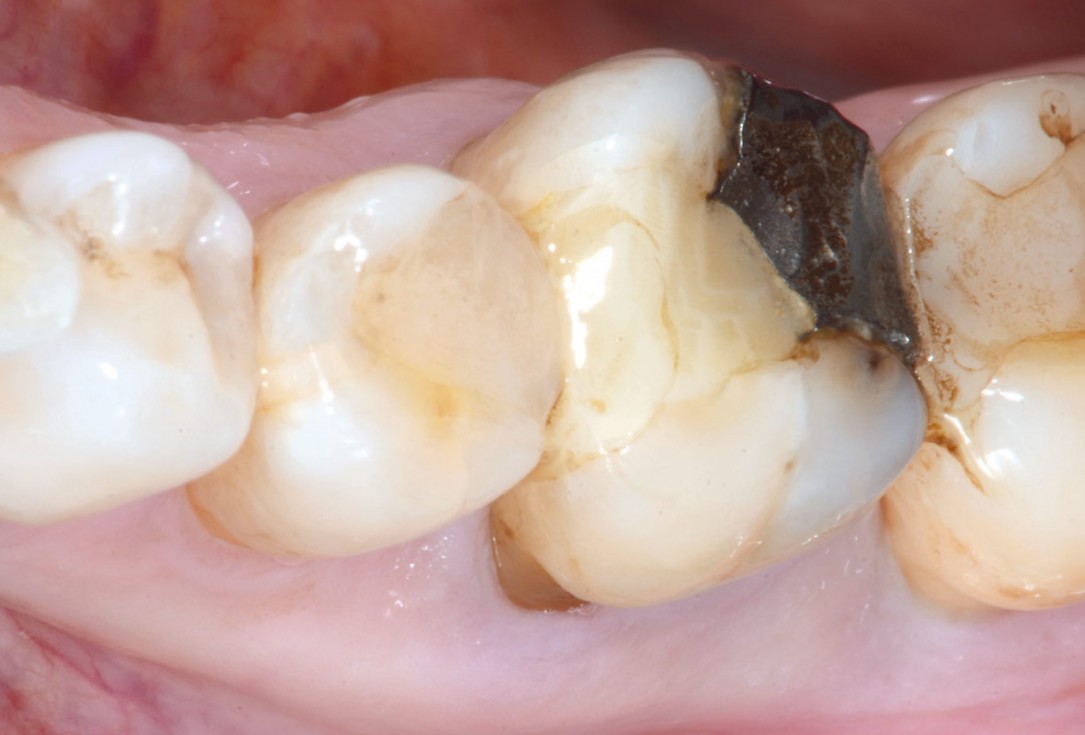

The patient presented with a terminal fracture of the crown tooth number 12